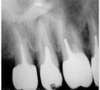

Dépose d’un tenon anatomique coulé à l’aide de la trousse de Gonon